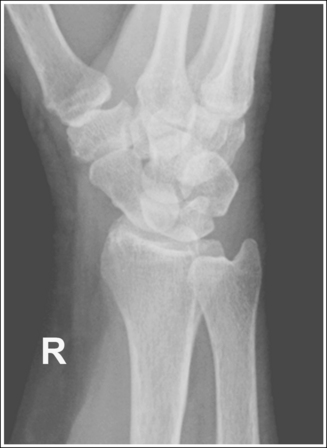

See Figure 4-29 and Box 4-11.

The wrist is positioned in a PA projection. The radial and ulnar styloids are at the extreme lateral and medial edges, respectively, of each bone. The radioulnar articulation is open, and superimposition of the metacarpal bases is limited.

• Rotation of the wrist and forearm is controlled by the position of the hand, elbow, and humerus. A PA projection is accomplished by abducting the humerus until it is positioned parallel with the IR and the elbow is in a lateral projection. The hand is then pronated, placing the wrist in a PA projection (Figure 4-31).

• Detecting wrist rotation and radial styloid position. When the hand and wrist are rotated externally into an externally rotated PA oblique projection, the carpal bones and metacarpal bases located on the medial aspect of the wrist are superimposed, whereas those located laterally are not. The lateral interconnecting carpal and metacarpal joint spaces are also demonstrated (see Image 31). Internal rotation of the hand and wrist causes the laterally located carpal bones and metacarpal bases to be superimposed and increases visibility of the pisiform and hamate hook (see Image 32).

• External and internal hand and wrist rotation also cause the radial styloid to rotate out of profile and closes the radioulnar articulation.

• Humerus and elbow positioning and ulnar styloid visualization. Humerus and elbow positioning determines the placement of the ulnar styloid. Abducting the humerus to position the elbow in a lateral projection with the humeral epicondyles aligned perpendicularly to the IR brings the ulnar styloid in profile and aligns the radius and ulna parallel with each other. The ulna and radius cross each other if the humerus is not abducted but is allowed to remain in a vertical position with the humeral epicondyles closer to parallel with the IR. This inaccurate positioning can be identified on a PA wrist projection by viewing the ulnar styloid, which is no longer demonstrated in profile (see Image 38).

The carpal bones are at the center of the exposure field. The carpal bones, one fourth of the distal ulna and radius, and half of the proximal metacarpals are included within the collimated field.

• The wrist joint is located at a level just distal to the palpable ulnar styloid. To obtain an image of the carpal bones with the least amount of distortion, place a perpendicular central ray at this level and centered to the midwrist area. Open the longitudinal collimation to include half of the metacarpals. Transversely collimate to within 0.5 inch (1.25 cm) of the wrist skin line.